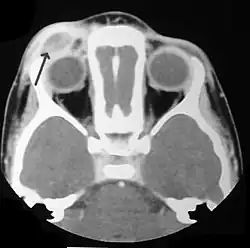

CT scan showing LCH infiltrating peri-orbital tissue (arrowed).